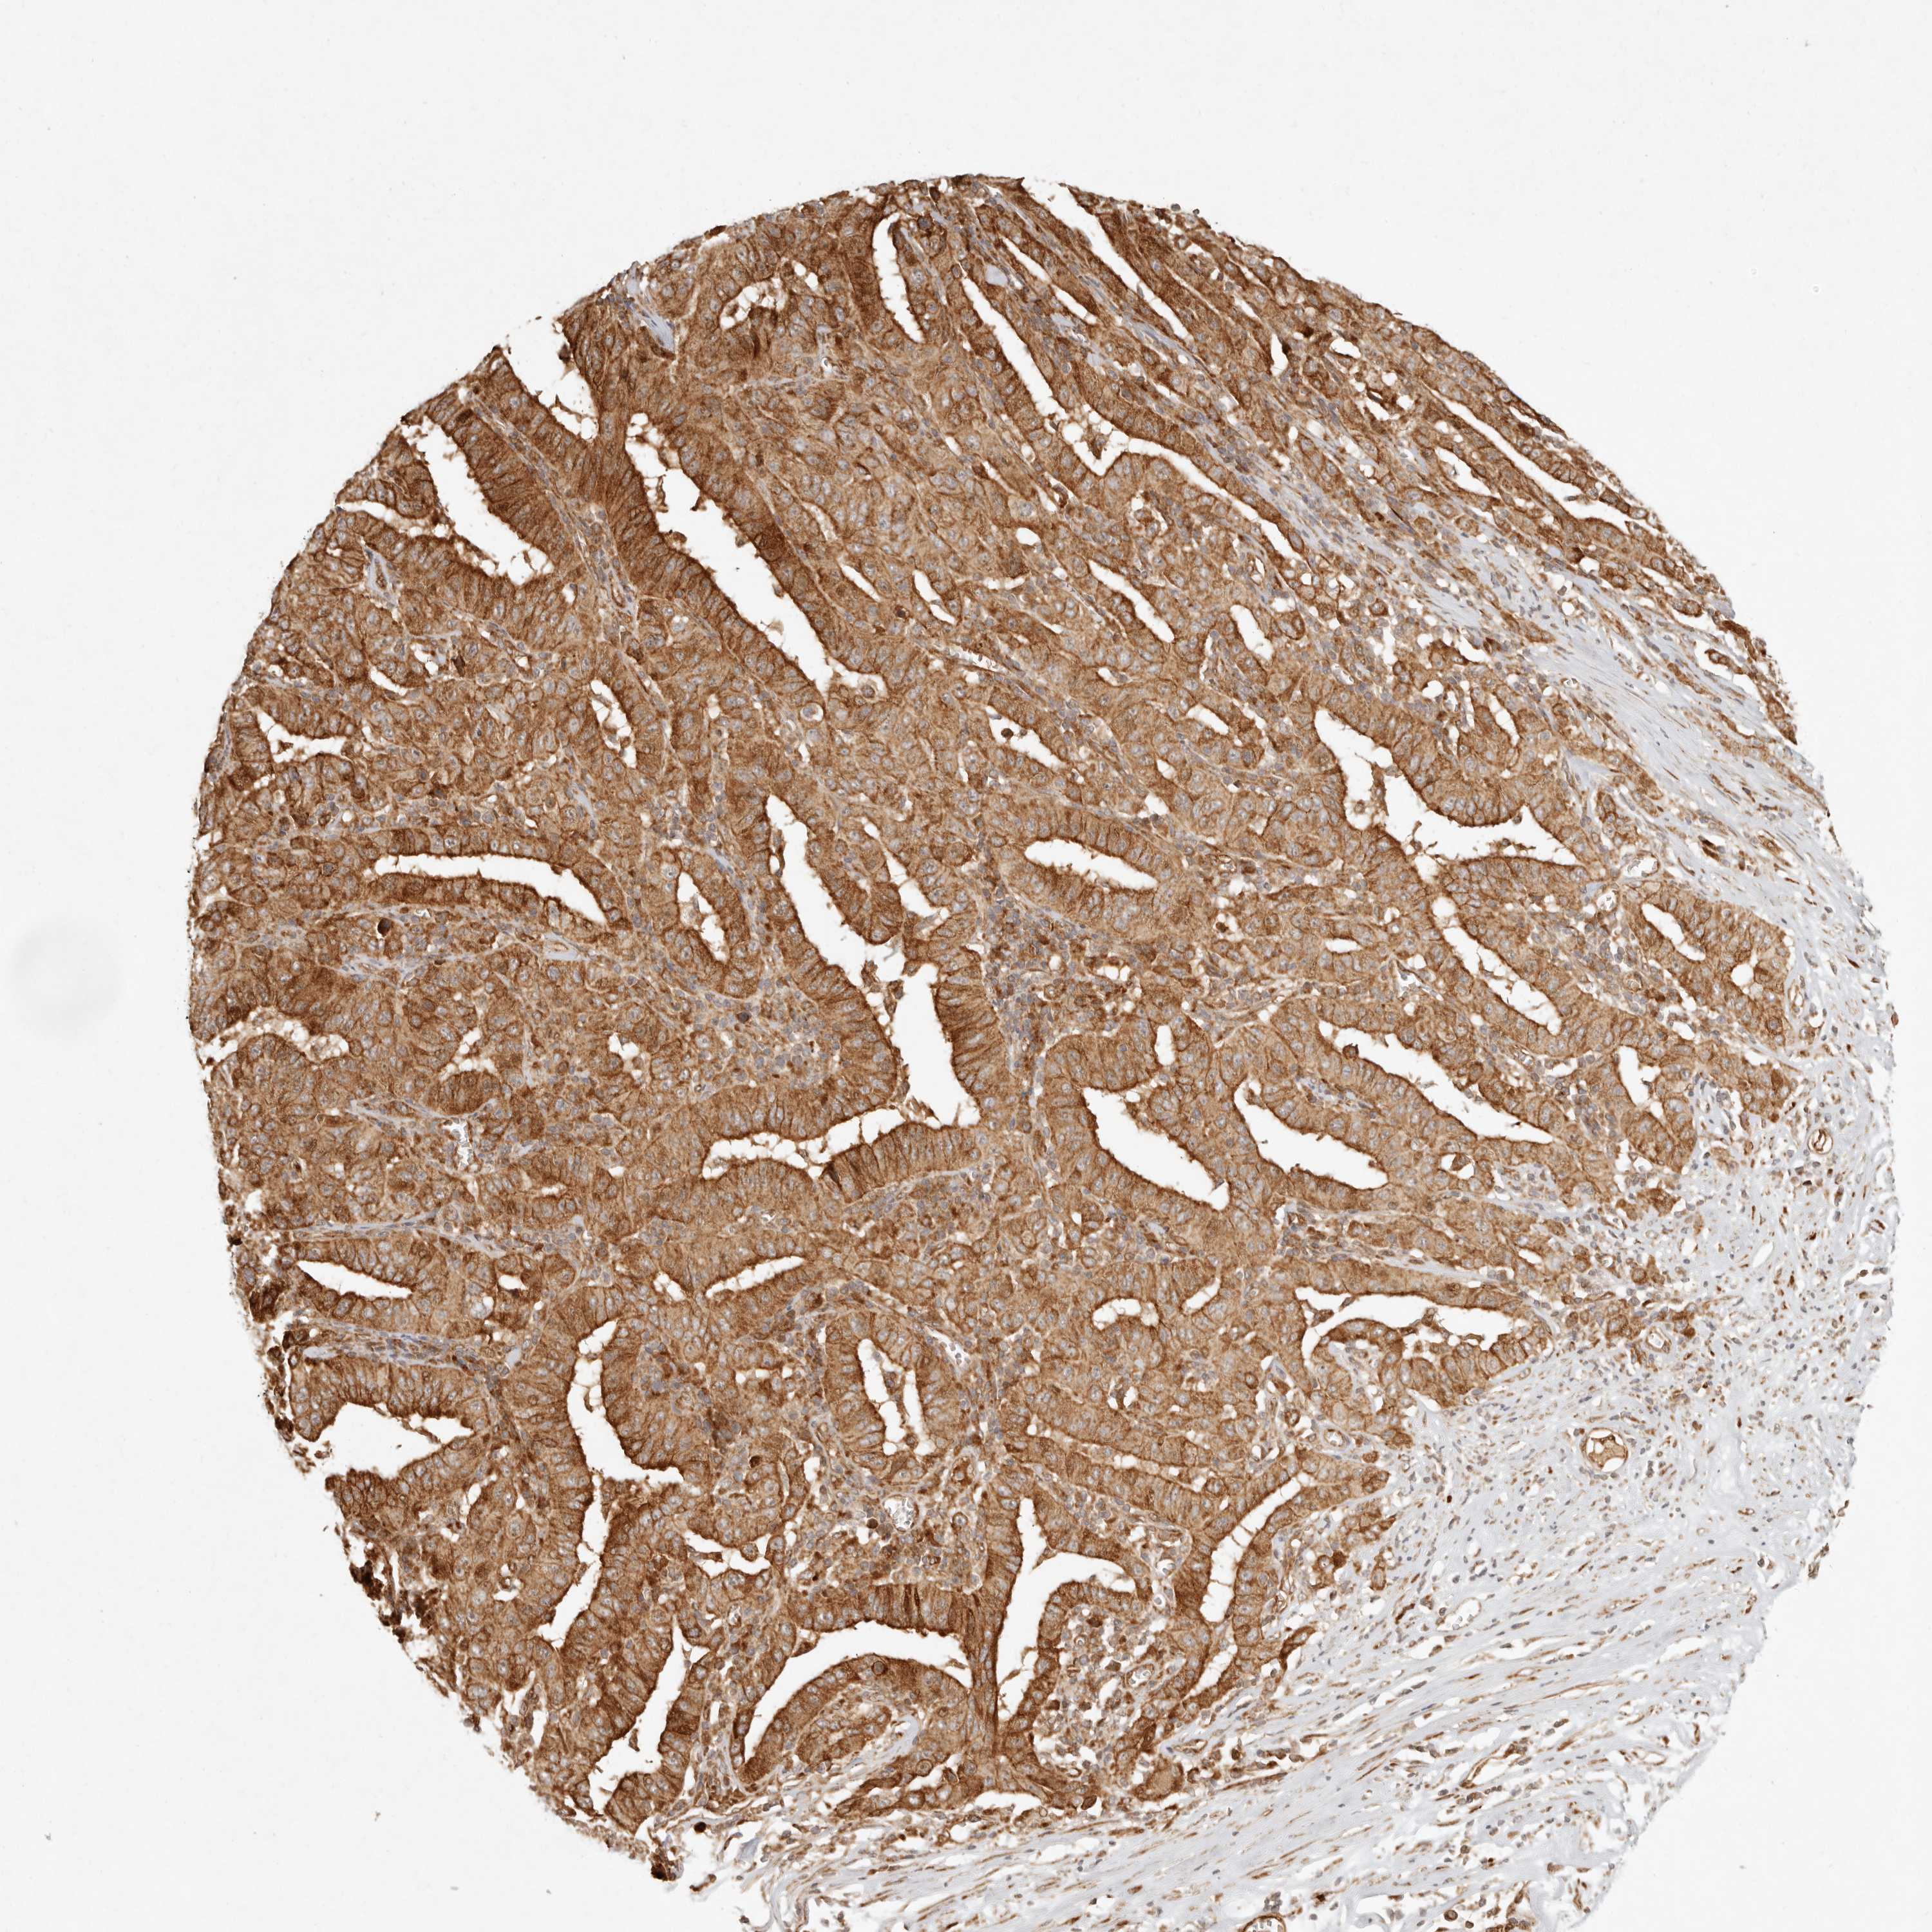

PANCREATIC CANCER - Protein expressioni

A mouse-over function shows sample information and annotation data. Click on an image to view it in a full screen mode. Samples can be filtered based on level of antibody staining by selecting one or several of the following categories: high, medium, low and not detected. The assay and annotation is described here.

Note that samples used for immunohistochemistry by the Human Protein Atlas do not correspond to samples in the TCGA dataset.

Antibody stainingi

Antibody staining in the annotated cell types in the current human tissue is reported as not detected, low, medium, or high, based on conventional immunohistochemistry profiling in selected tissues. This score is based on the combination of the staining intensity and fraction of stained cells.

Each image is clickable and will lead to virtual microscopy that enables deeper exploration of all samples and also displays staining intensity scores, fraction scores and subcellular localization as well as patient and tissue information for each sample.

Antibody HPA024770

Antibody HPA027115

Staining

High

Medium

Low

Not detected

Intensity

Strong

Moderate

Weak

Negative

Quantity

>75%

75%-25%

<25%

None

Location

Nuclear

Cytoplasmic/membranous

Cytoplasmic/membranous,nuclear

Adenocarcinoma, NOS